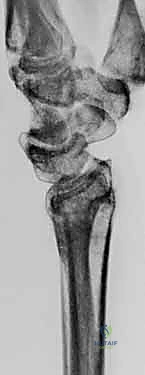

عند حدوث التئام معوج (Malunion)، تتغير هذه الزوايا. على سبيل المثال، إذا فقدت الكعبرة طولها (أصبحت أقصر من الزند)، فإن عظم الزند سيصطدم بعظام الرسغ الصغيرة (Ulnar Impaction Syndrome)، مما يسبب تمزقاً في الغضروف الثلاثي (TFCC) وألماً مبرحاً عند دوران اليد.

- الأشعة السينية الرقمية (X-rays): للرسغين السليم والمصاب، لمقارنة الزوايا وحساب مقدار التشوه بدقة.

- الأشعة المقطعية (CT Scan) مع إعادة البناء ثلاثي الأبعاد (3D Reconstruction): هذه الخطوة حاسمة. تتيح للدكتور هطيف رؤية العظم من جميع الزوايا، وتحديد مكان القص بدقة متناهية.